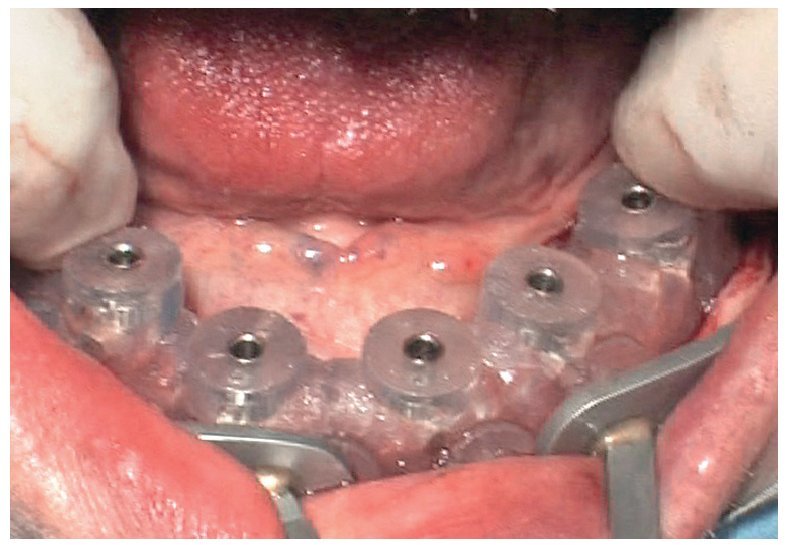

Fig. 69. Los implantes y las cofias provisionales para prótesis atornilladas colocados en el maxilar inferior.